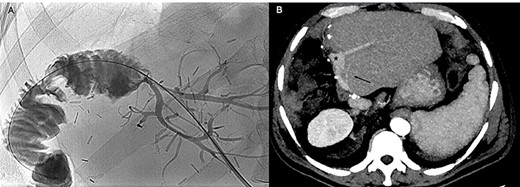

Under local anesthesia and conscious sedation, the right and middle hepatic veins (HVs) were accessed under ultrasonographic guidance with 21G Chiba needles, 0.018″ guidewires and micropuncture sets (Meditalia Biomedica, Medolla, Italy) (Fig. 2A).

After US-guided percutaneous transhepatic access with micropuncture sets (A) the right and middle HVE was performed using two 90% oversized vascular plugs (B) and then completed with 2:1 Lipiodol-glue mixture (C), resulting in a 26.8% increase in volume of the FLR (501 vs. 395 cc) after 9 days with a kinetic growth rate (KGR) of 11.8 cc/days (D, E).

Two 0.035″ guidewires (Amplatz Super Stiff, Boston Scientific, Marlborough, MA) were advanced to the atrio-caval junction and, after accommodation of two 8F × 24 cm sheaths (Radifocus Introducer II, Terumo, Japan), 6 and 7 mmHg of endoluminal pressure were measured, respectively, in the right and middle HVs. After that, both HV were occluded with Amplatzer Vascular Plugs II (St-Jude Medical, Plymouth, MN), respectively, 22 and 16 mm in diameter (90% oversized), with the distal part deployed 10–15 mm proximal to the junction with the inferior vena cava to enable further surgical ligation (Fig. 2B). The embolization of the HVs and potential collaterals was distally completed with a 2:1 mixture of Lipiodol Ultrafluid (Guerbet, Villepinte, France) and Glubran 2 (GEM Italy, Viareggio, Italy) (Fig. 2C).

The CECT scan performed 9 days after the HVE showed a 26.8% increase in volume of the FLR (501 vs. 395 cc), resulting in a kinetic growth rate (KGR) of 11.8 cc/day. FRL/TLV ratio was 20.4% (+5.5%) and the FRL/sTLV ratio was 25.1% (+ 5.3%) (Fig. 2D and E).